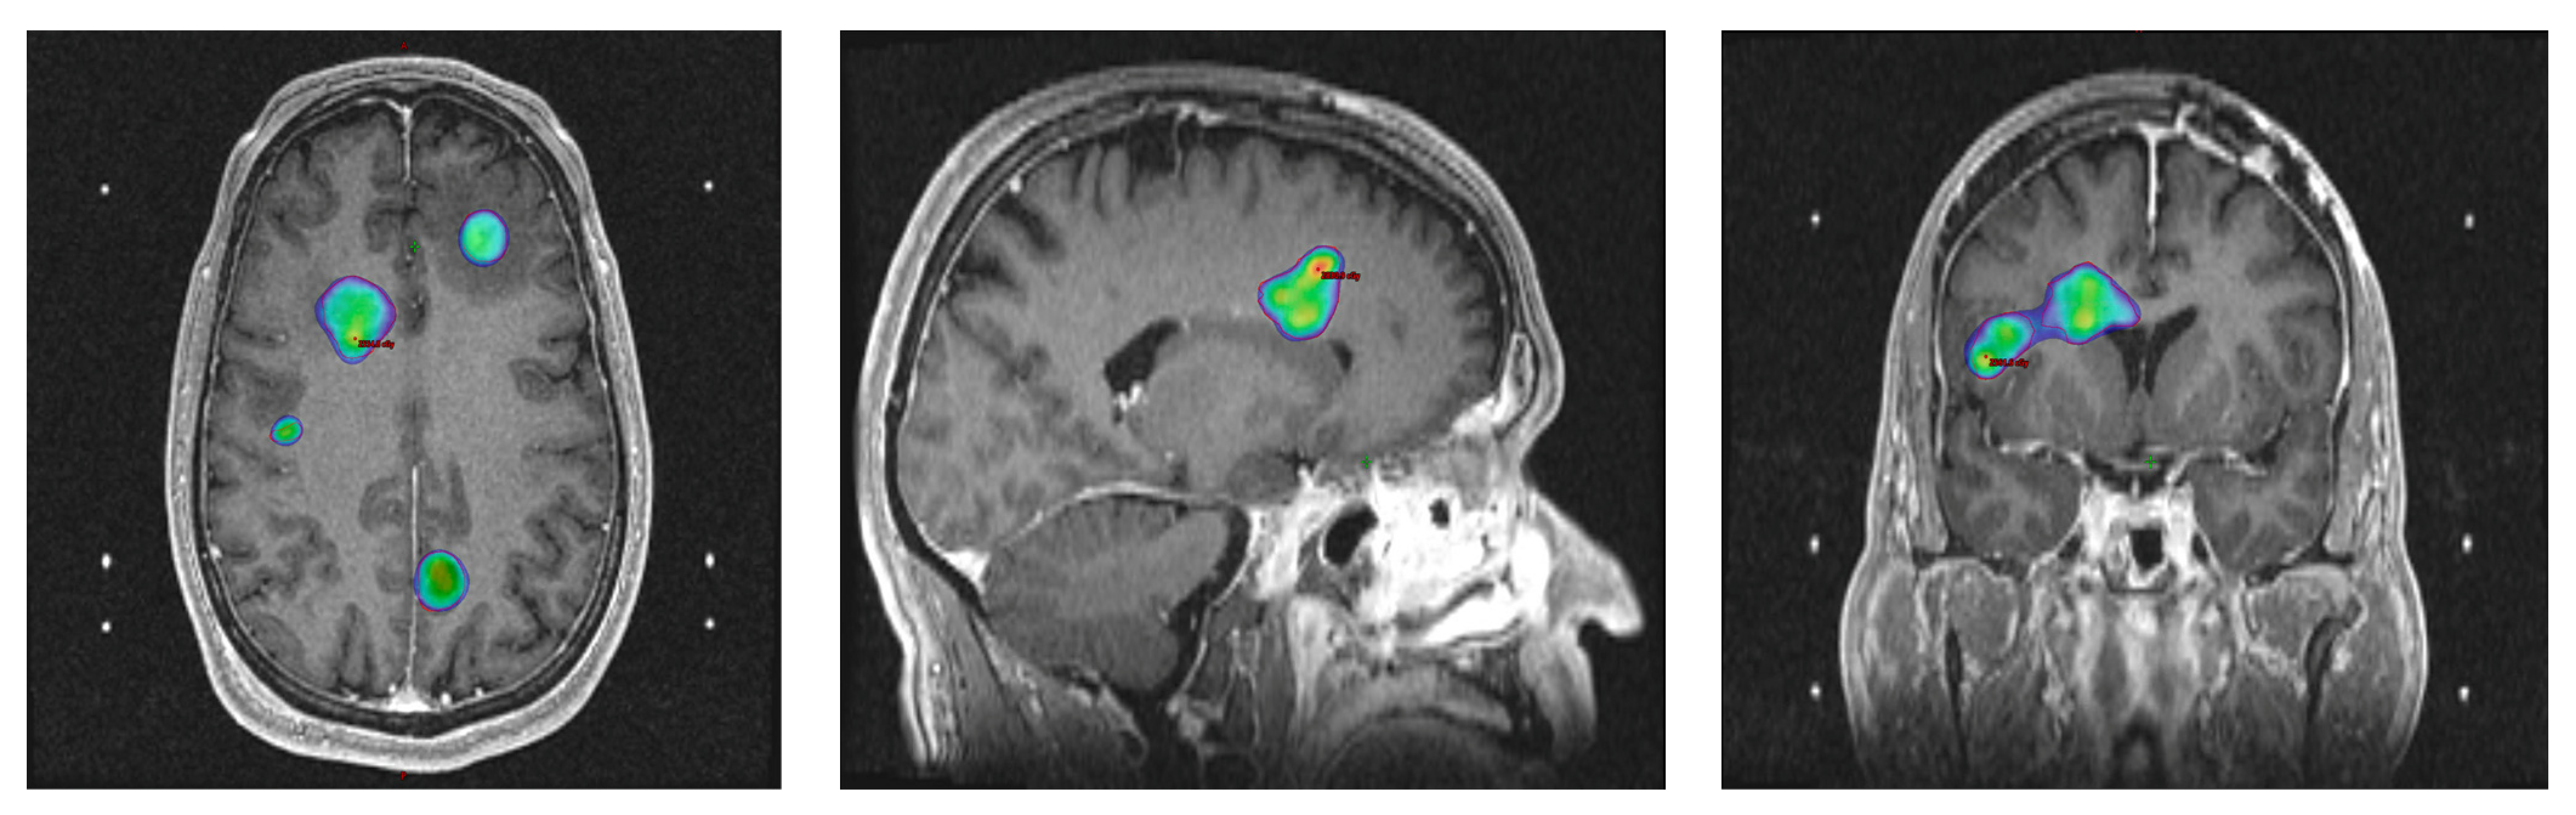

- Akbari, H.; Macyszyn, L.; Da, X.; Bilello, M.; Wolf, R.L.; Martinez-Lage, M.; Biros, G.; Alonso-Basanta, M.; O’Rourke, D.M.; Davatzikos, C. Imaging Surrogates of Infiltration Obtained Via Multiparametric Imaging Pattern Analysis Predict Subsequent Location of Recurrence of Glioblastoma. Neurosurgery 2016, 78, 572–580. [Google Scholar] [CrossRef]